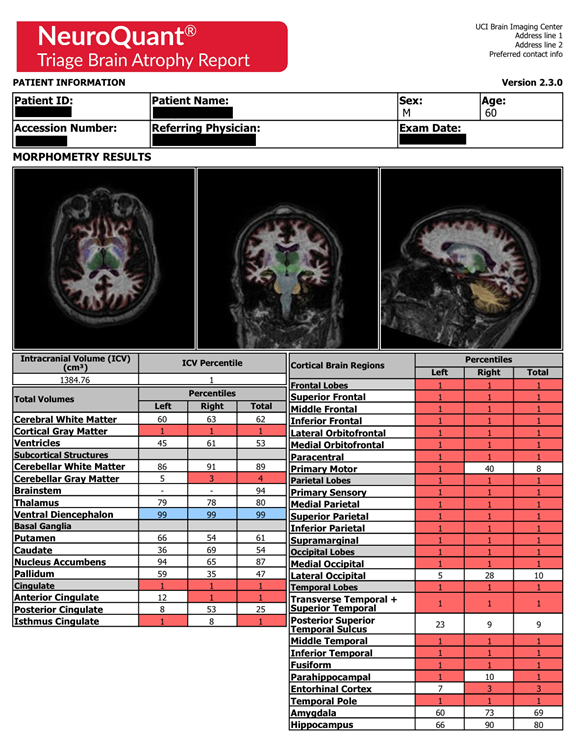

MRI brain quantitative volume analysis

Statistical analysis of NeuroQuant volumetric measures of MRI data shows a significant reduction in left and right forebrain parenchyma and left and right cortical gray matter in absolute and relative terms, which is more pronounced in relative terms on the right side. The defendant shows significant enlargement in the right lateral ventricle in relative terms. He shows a reduction in the left hippocampus, left amygdala, and left caudate and right putamen in absolute terms. He shows a bilateral reduction in the thalamus and cerebellum in absolute terms. Data shows a significant reduction in intracerebral volume in absolute terms. These findings are consistent with damage from premature birth, TBI, and severe childhood emotional abuse. The predominantly left sided nature of the atrophy noted in brain structures such as the hippocampus and the amygdala would be consistent atrophy secondary to multiple traumatic brain injuries from having been beaten in the head repeatedly by his abusive mother when he was growing up.

From Quantitative Volumetric analysis, the defendant shows significantly lower brain volume compared to normal, very significant reduction in left and right forebrain parenchyma, which is more pronounced on the left than the right. The reduction in his left forebrain parenchyma is more than six standard deviations below the mean. That means these findings would be seen in only 8.7 out of ten billion people. The quantitative volumetric analysis also shows left-sided asymmetrical decreases in the hippocampus and amygdala. Left-sided atrophy to the hippocampus and amygdala would be consistent with being hit on the head multiple times by a right-handed person. The reduction in left forebrain parenchyma and the left sided asymmetrical decrease in hippocampus and the amygdala would also be consistent with atrophy secondary to chronic temporal lobe epilepsy on the left side. This left-sided reduction would also be consistent with the abnormal increase in left inferior temporal lobe metabolism and left thalamus (see above PET discussion), and with abnormal decrease in FA in the left internal capsule, left anterior corpus callosum (see above DTI Discussion). This left-sided reduction would also be consistent with an asymmetrical decrease in fiber track length of the left mid corpus callosum compared to the right side.

Neuroquant general and triage brain atrophy report

NeuroQuant General and Triage Brain Atrophy Reports show multiple cortical sub-regions were in the 1st percentile including Intracranial Volume (ICV) of 1384.76 cm3 (Table 1). Multiple brain regions were noted to be in the 1st percentile on the Brain Triage atrophy report (Table 2).

Table 1 NeuroQuant General Brain Atrophy Report shows relative small volume in both left and right forebrain parenchyma, putamen, cerebellum, and left hippocampus that support defendant’s high risk of TBI, early severe childhood abuse, and high risk of CTE

Table 2 NeuroQuant Triage Brain Atrophy Report. NeuroQuant provides forty-two of the brain’s regional and lobe structure volumes. Report evaluated abnormalities that may show risk of neurodegenerative diseases in red font